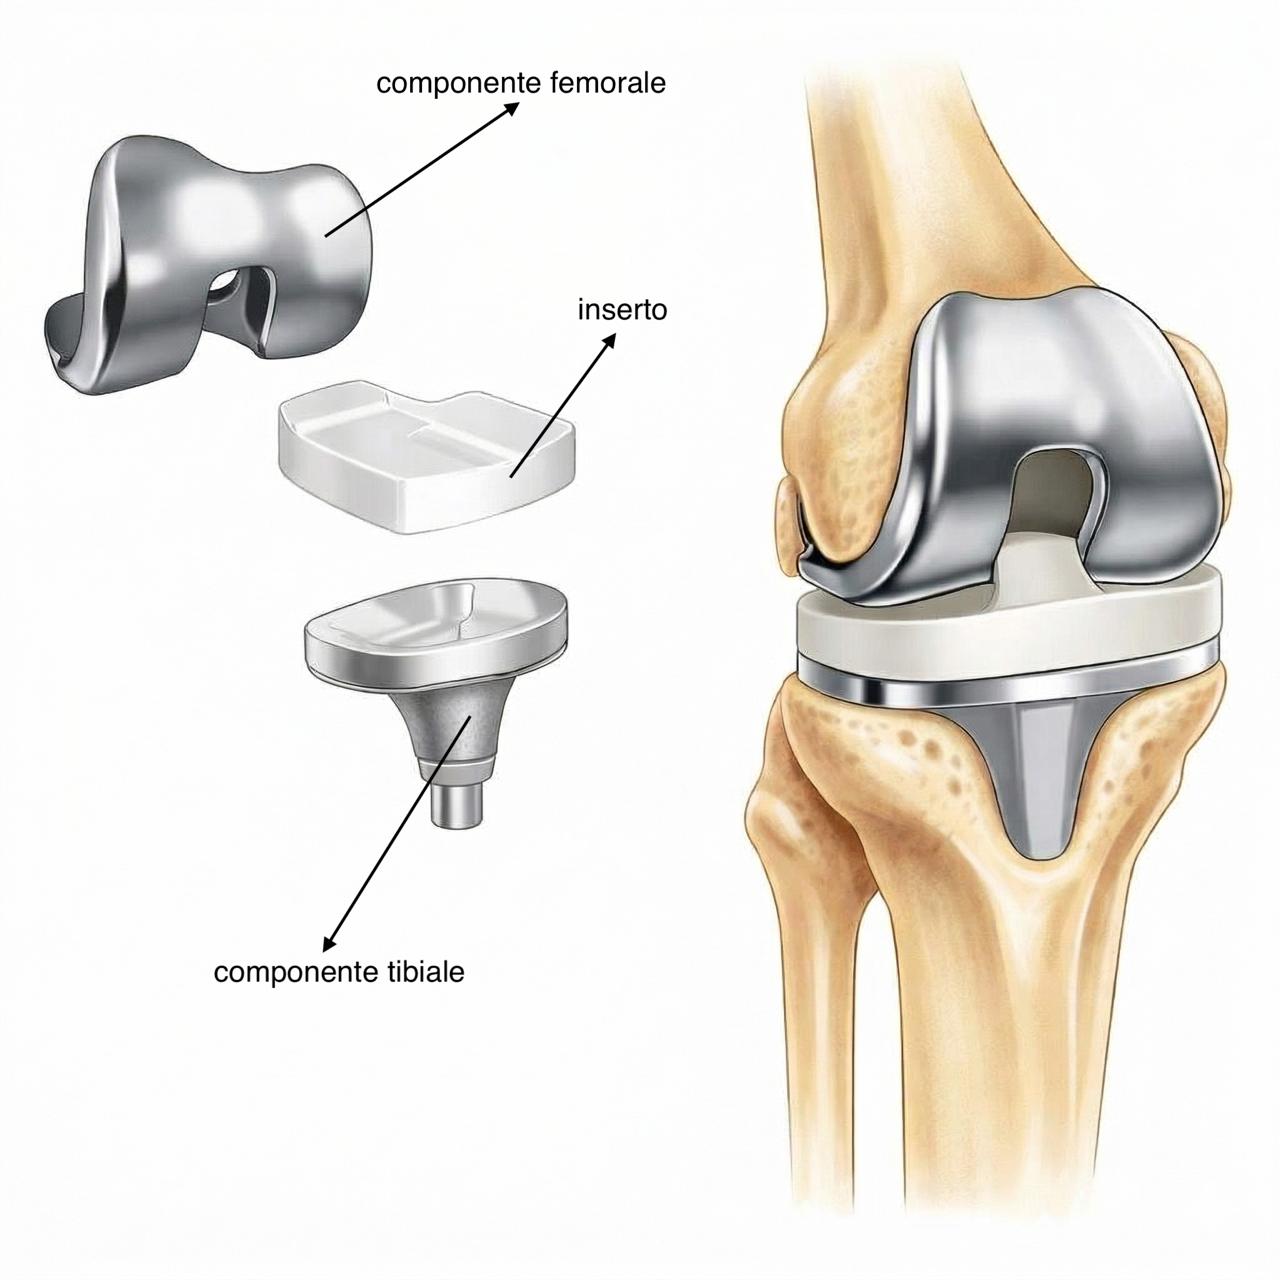

Quando le terapie conservative non sono più efficaci, si esegue protesi totale o parziale.